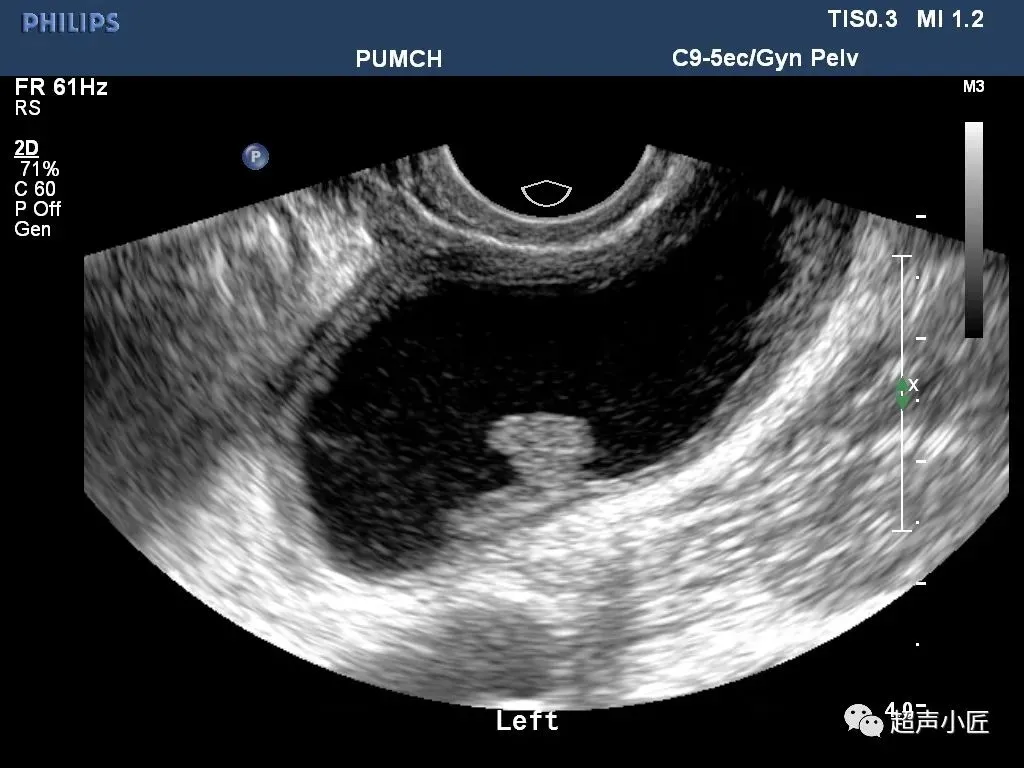

●卵泡囊肿(成熟卵泡未破裂):多呈圆形;大小多为2-3cm,囊壁薄而光滑;囊液清亮;囊肿多位于子宫一侧或侧后方,多为单侧。

●黄体囊肿(多见于子宫内膜分泌期或妊娠早期):大小多为2-3cm或更大;个别黄体囊肿可破裂出血而出现急腹症。